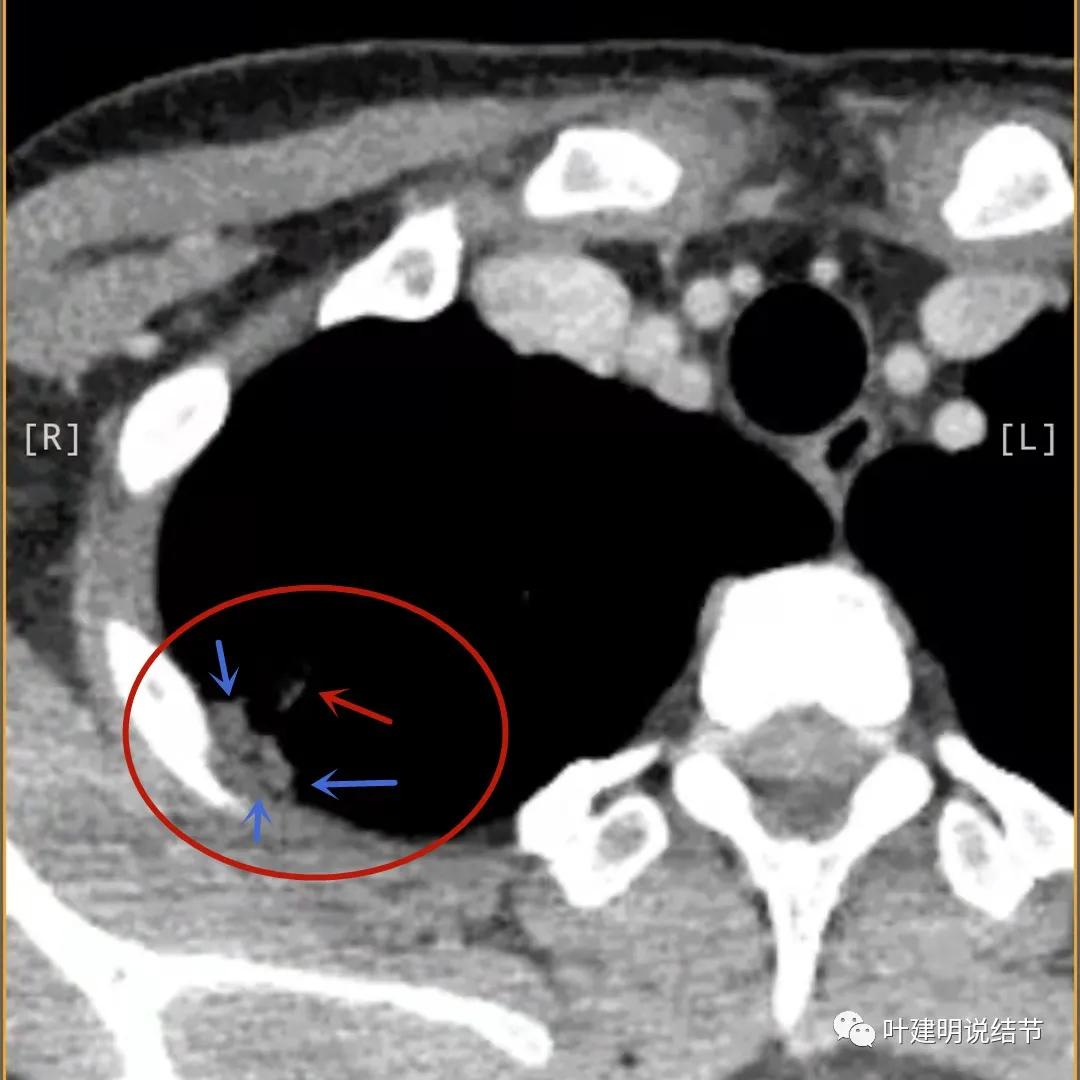

蓝色箭头所指处居然有低密度影,难道是坏死?因为比肌肉密度低,也无强化,况且主病灶的中间也有个低密度的小点状

邻近胸膜处的增厚密度低于肌肉组织,病灶强化明显且均匀

此层也见明显的低密度区域(天蓝色箭头)

胸膜处明显增厚伴低密度区域

天蓝色箭头示病灶低密度区,考虑坏死可能性大,桔色箭头示边缘凹陷无膨胀性

上图示空洞偏心,而且红色箭头所指处与空腔似乎是整合,而非囊壁生长增厚。天蓝色箭头示近胸膜处的低密度区域,考虑坏死成分,囊壁的邻近部分也是极低密度区域,也可能是干酪样坏死区